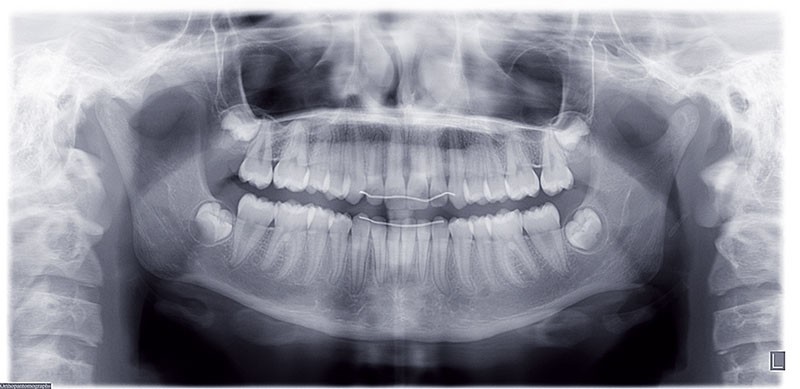

Nous sommes en présence d’une patiente adolescente âgée de 12 ans ½ dans une phase de croissance faciale favorable.

Elle présente une classe II squelettique par rétrognathie mandibulaire et une classe II dentaire molaire et canine droite et gauche associée à une biproalvéolie incisive maxillaire et mandibulaire.

L’environnement vertical est normodivergent.

Le pronostic de correction de la classe II est favorable mais il est très important de souligner la vestibuloversion incisive mandibulaire et le risque parodontal associé (fig. 1 à 3).